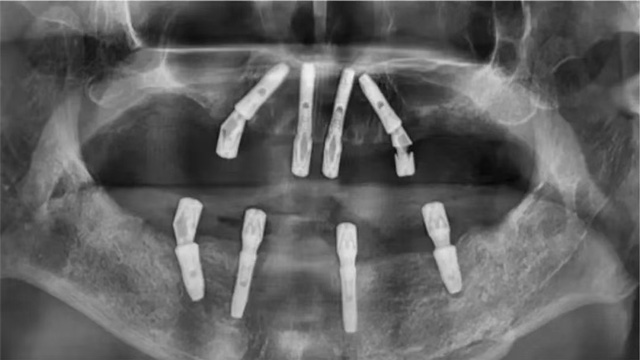

新年到來(lái)之前,張先生接受了全口種植治療。姜辰主任先對(duì)他口腔內(nèi)的松動(dòng)牙進(jìn)行了拔除,拆除原有種植體,完成清創(chuàng)和炎癥組織清理后,重新種上了8顆新的種植體。手術(shù)過(guò)程順利,同時(shí)創(chuàng)傷輕微。

術(shù)中拆除的6顆種植體